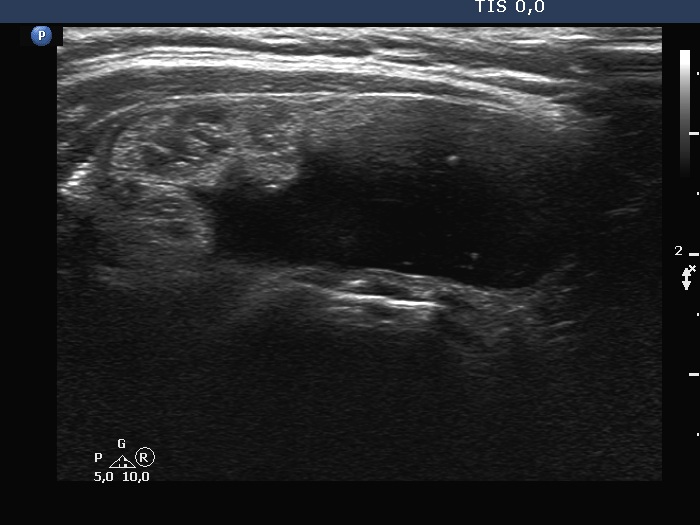

The nodule, which was previously described in the left lobe, seemed to be located in the isthmus. The dimensions of this lesion were 36x18x40 mm, width, depth, length, respectively. Except for the significant increase in size, the pattern of the nodules remained unchanged. Several small, hypoechoic discrete lesions were found in the left lobe.Cytology was performed form both nodules and resulted in follicular tumor and benign cystic-colloid goiter, right and left nodule, respectively. The cyst could not be emptied, only a small amount of brown fluid could be aspirated.

The ultrasound presentation of the nodule in the left lobe or in the left side of the isthmus was typical of a benign cystic lesion. The back wall figures were misinterpreted as microcalcifications.

Depending on the positioning of the tranducer, nodules located at the isthmic part of a lobe can be projected as it were within the lobe or in the isthmus.